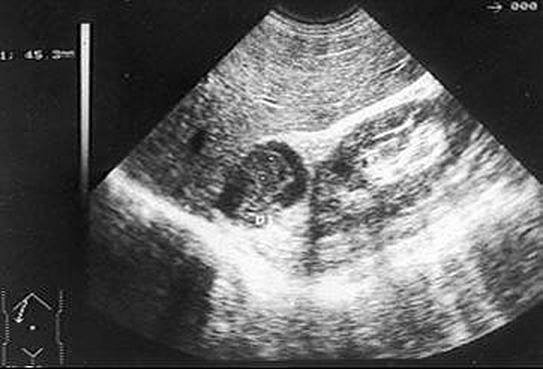

Los síntomas de adenoma suprarrenal pueden estar ausentes si el adenoma no afecta a la parte de las glándulas suprarrenales que secretan las hormonas. Por lo tanto, el diagnóstico de adenoma suprarrenal sin repercusión clínica se realiza por casualidad a través de técnicas de imagen abdominal, como ultrasonido, Tomografía o Resonancia magnética, o en algunos casos  de una dosificación en sangre que muestran un aumento de las hormonas secretadas por el adenoma. En caso de exceso de producción de cortisol, los signos clínicos de la hipersecreción corresponden al llamado síndrome de Cushing. Este síndrome se diagnostica por las pruebas hormonales en un análisis de sangre . Algunas pruebas requieren tomar un producto y realizar diferentes dosificaciones programadas en diferentes momentos

La Tomografía axial es hoy en día la exploración por excelencia utilizada para explorar la morfología de la glándula suprarrenal. Nos brinda la posibilidad de medir las características de absorción de la estructura a estudio, y dar un diagnóstico certero.